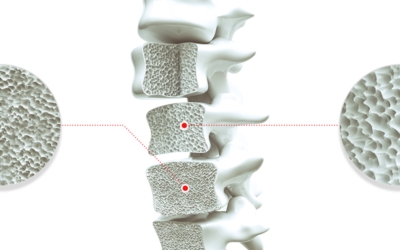

골다공증이란

골다공증이란 단단해야 할 뼈가 약해져서 부러지기 쉬운 상태가 되는 질환을 말해요. 골다공증이란 이름 그대로 약해진 뼈에 구멍이 송송 관찰되는 모습 때문에 지어진 명칭입니다. 나이가 들어가면서 관절이 약해지고 골다공증 으로 고생하게 돼요. 골다공증은 노화때문에만 발생되는 것이 아니랍니다.

작은 쇼크을 받아도 다치기 어렵지 않고 골절이 쉽게 오는 골다공증 증상은 과한 다이어트, 음주, 흡연, 규칙적이지 않은 식생활로 젊은분들에게도 골다공증이 많이 나타나고 있습니다. 여성의 경우, 폐경 후에 여성호르몬 분비가 다운되어 골밀도가 저하되므로 뼈가 스펀지처럼 되어 골절이 쉽게 오는 것으로 보입니다. 대퇴골, 손목 척추, 발목 부위에서 주로 골절이 발생하기 때문에 평소 골다공증에 좋은 음식 또는 스트레칭, 수영, 가벼운 산책 과 같은 저강도 운동을 하시는 게 좋겠네요.